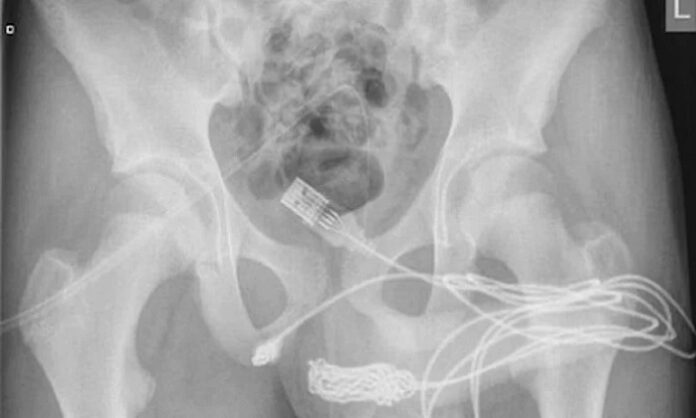

Yaşadığı olayı kaldırıldığı hastanede doktorlara anlatan gencin röntgen sonucunu inceleyen bilim insanları ise şaşkına döndü. “Cinsel deney” uğruna sağlığını riske atan gencin penisinden USB kablo zorlukla çıkarıldı.

Ameliyatı gerçekleştiren doktorlar durumu kamuoyuna hazırladıkları bir rapor ile duyururken, USB kablolarının vücut içinde düğüm olduğunu ve bu sebeple ameliyatın büyük bir zorluk içerisinde gerçekleştiğini açıkladı.

Science Direct isimli medya platformunun Urology isimli bilimsel dergiden hazırladığı haberde yer alan bilimsel araştırmada olayın 2021’de meydana geldiği belirtildi. Doktorların kaleme aldığı bilimsel araştırmada, “Vücuda yerleştirilen cisim derin doku üzerinden çıkarıldı. Kablolar penis ucundan çıkarıldı” denilirken ismi açıklanmayan gencin cinsel deney için bunu yaptığı ve herhangi bir zihinsel rahatsızlığı olmadığı da duyuruldu.